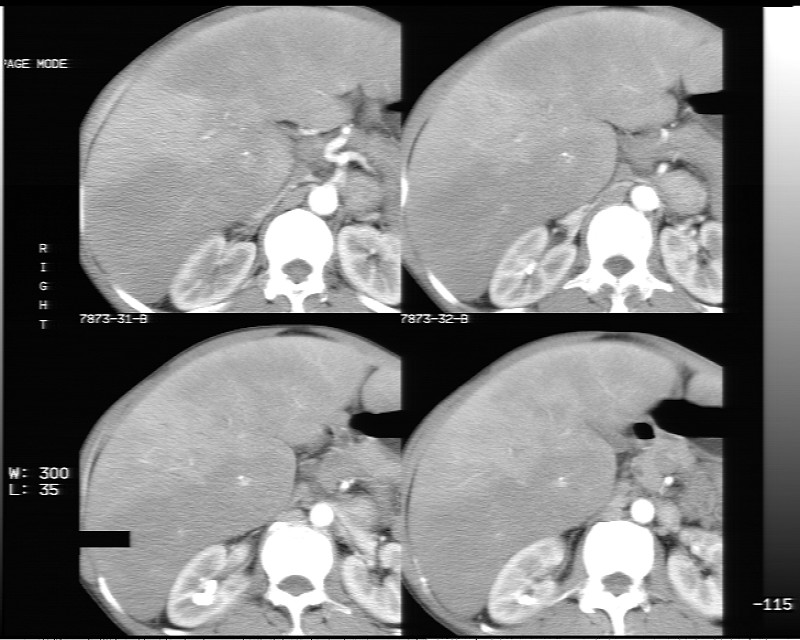

平扫示:

不均匀性脂肪肝

不均匀性脂肪肝 。支持!

非均质性脂肪肝。

不均匀性脂肪肝。

支持脂肪肝【无占位性,高低密度区同期强化,平扫与强化的密度成比例】

不均匀性脂肪肝。肝脏体积稍大,不除外合并肝功能损害。